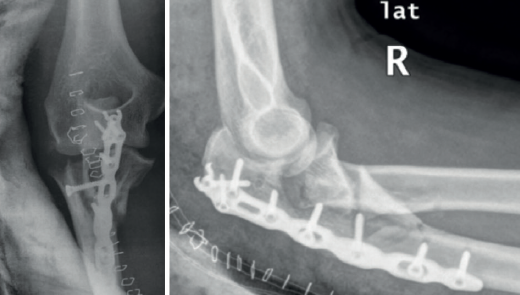

Cuando la fractura del olécranon incluye una fractura de la coronoides, la reducción y la fijación de esta es condición imperativa para conseguir la estabilidad humerocubital (Figuras 7, 8 y 9). La reducción puede llevarse a cabo a través de la fractura del olécranon o por medio de un abordaje medial, separando o a través de la musculatura flexora/pronadora, teniendo identificados y protegidos el nervio cubital y el fascículo anterior del ligamento colateral medial. En los casos en los que es necesario realizar la sustitución de la cabeza del radio por una prótesis, también es posible el acceso lateral a la fractura de la coronoides. En general, el fragmento permite la fijación con tornillos desde posterior a anterior, a través de la placa posterior o independientes de esta, o en ocasiones desde anterior a posterior. La utilización de placas de 2,7 mm o específicas de coronoides, y técnicas de suturas no reabsorbibles atadas sobre el cúbito proximal o sobre la placa de fijación del cúbito son otras opciones(13,17). Para los grandes defectos óseos o fracturas irreconstruibles de la coronoides, se han descrito injertos óseos de la cresta ilíaca e injertos osteocondrales de la cabeza del radio con resultados impredecibles debido a la osificación heterotópica y a la reabsorción ósea del injerto(20,21).

Las fracturas complejas del cúbito que afectan al olécranon o a la coronoides pueden fijarse de “proximal a distal”(1) o de “distal a proximal”(22) en función de lo que resulte más fácil en cada caso. En la fijación de “proximal a distal”, el fragmento proximal del olécranon se fija temporalmente a la tróclea con una o varias agujas de Kirschner de 1,5 mm y el cúbito se reduce sobre el fragmento de olécranon proximal. La fijación de “distal a proximal” se centra inicialmente en la reducción y la fijación de los fragmentos distales del cúbito con objeto de simplificar los trazos de fractura y finalmente proceder a la reducción y la fijación con el fragmento proximal del olécranon. En la reconstrucción de la escotadura mayor del olécranon, se deben tener en cuenta la relación anatómica normal de la coronoides con el olécranon y la existencia de la zona desprovista de cartílago en la escotadura mayor. La incongruencia articular en las fracturas conminutas tiene menos impacto en el resultado clínico que la falta de alineación, altura y rotación de la escotadura mayor del olécranon(1).